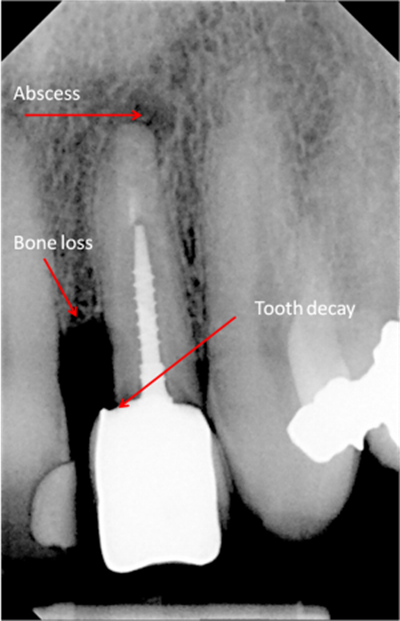

Digital x-rays can be used to diagnose:

• Cysts of jawbone

• Bone loss

• Cancerous and non-cancerous bony lesions

• Decay between teeth

• Development abnormalities

• Poor tooth and root positions

• Impacted teeth

bone loss